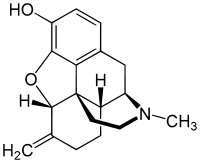

Morphine

In the 19th century, two major scientific advances were made that had far-reaching effects. Around 1804, German pharmacist Friedrich Sertürner isolated morphine from opium. He described its crystallization, structure, and pharmacological properties in a well-received paper in 1817.[211][213][208][214] Morphine was the first alkaloid to be isolated from any medicinal plant, the beginning of modern scientific drug discovery.[211][215]

Morphine was initially hailed as a wonder drug for its ability to ease pain.[219] It could help people sleep,[211] and had other useful side effects, including control of coughing and diarrhea.[220] It was widely prescribed by doctors, and dispensed without restriction by pharmacists. During the American Civil War, opium and laudanum were used extensively to treat soldiers.[221][219] It was also prescribed frequently for women, for menstrual pain and diseases of a "nervous character".[222]: 85 At first it was assumed (wrongly) that this new method of application would not be addictive.[211][222]

- Natural opiates: alkaloids contained in the resin of the opium poppy, primarily morphine, codeine, and thebaine, but not papaverine and noscapine which have a different mechanism of action

Opium alkaloids and derivatives

Phenanthrenes naturally occurring in (opium):